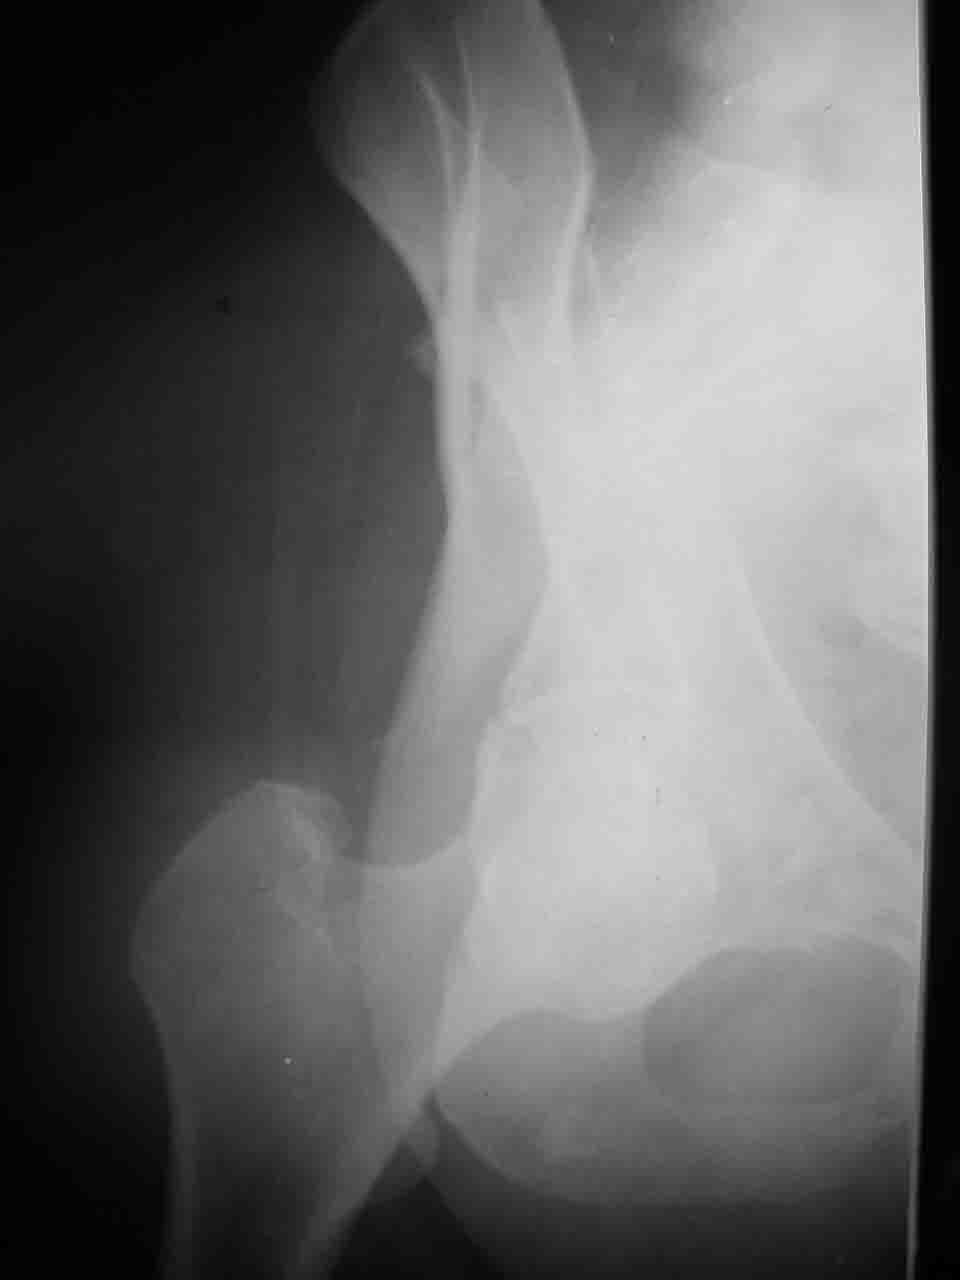

Интерес к реконструкции вертлужной впадины у меня появился довольно-таки давно, но до недавнего времени как-то не ощущалась готовность к практической реализации, а местный подход достаточно консервативен - перелом срастется,

а далее будет видно. Такую точку зрения я не разделяю, поэтому через конференции,ортофорум и свои случаи пытаюсь практически и теоретически *продвинуть* для себя тему реконструкции вертлужной впадины.

Логика подсказывает, что все-таки лучше иметь анатомически полноценную впадину, хотя ранее упоминалось состояние вторичной конгруэнтности и одно наблюдение у меня есть, когда у больного с полностью нарушенной анатомией впадины и подвывихом головки бедра кзади и кверху боли отсутствовали при относительно достаточном для стиля жизни больного объёме движений. Но это только одно наблюдение и кроме перелома впадины у этогобольного была и тяжелая ЧМТ в анамнезе. Основываясь на формулировке структуры ацетабулюм Э. Летурнеля - как перевернутой буквы Y, впадина для полноценной функции сустава должна иметь сферичность, соответствующую размеру головки бедра и если один из компонентов в дефиците, то функциональные последствия рано или поздно проявятся.

Сложностью, ассоциативностью характера перелома, я бы с радостью воспользовался мининвазивной перкутанной фиксацией винтами, но боюсь, что результат был бы ещё хуже, техникой непрямой репозиции перелома не владею, поэтому пытаясь получить анатомичную впадину приходится широко открывать, по крайней мере пока, а дальше буду пытаться уменьшать пространство...

Илеофеморальный доступ не совсем передний и сравнительно с илеоингвинальным, и Кохера-Лангенбека открывает весь наружный таз кроме самых передних отделов лонных костей, фиксацию которых я не ставил в задачу. Обширность диссекции, большая длительность операции и более высокий риск гетерооссификации - отрицательные моменты в обмен на возможность легче ориентироваться.

Вопрос доступа к вертлужной впадине при остеосинтезе задача не простая. Конечно, у Летурнеля и Тайла всё давно описано, нам остается только брать на вооружение. Но сами понимаете, что не бывает двух одинаковых ситуаций, поэтому в каждом случае вопрос решается сугубо индивидуально. Наша главная цель - восстановить анатомию с нанесением минимальной дополнительной травмы тазобедреннному суставу, думаю с этим никто не поспорит. Расширенный илиофеморальный доступ уж слишком травматичен (как сказал один коллега "таз лежит отдельно, больной отдельно").Стоит ли делать из пациента анатомический препарат для того чтобы легче ориентироваться. Да и нужно ли собирать всю "мозаику"? Мы применяли при таких операциях своеобразную операционную хитрость - сначала устраняли грубое смещение крыла под гребнем с фиксацией так называемой "плавающей" пластиной (временно фиксированной на двух винтах)- доступ или продлевали боковой, или делали небольшой дополнительный разрез над гребнем. Это позволяло устранить грубое смещение и захождение отломков тела повздошной кости, что значительно облегчало репозицию и остеосинтез впадины над сводом. Основное внимание конечно же уделяли нагружаемому задне-верхнему отделу. Сообщите ваш адрес, пришлю схемы и рентгенограммы.